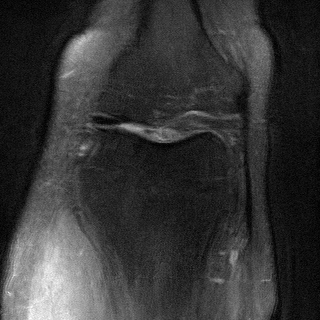

Side

Measurement

ContextMRI

RFJSearch (Ours)

Ground Truth

PDFS with PD

PD with PDFS

| PDFS with PD | ||||

|---|---|---|---|---|

| Algorithm | PSNR () | SSIM () | LPIPS () | NMI () |

| RFJS | 25.85 | 0.801 | 0.375 | 0.457 |

| GS | 25.33 | 0.797 | 0.375 | 0.455 |

| BON | 25.47 | 0.797 | 0.376 | 0.454 |

| ContextMRI | 25.39 | 0.795 | 0.383 | 0.451 |

| PD with PDFS | ||||

| RFJS | 27.85 | 0.920 | 0.358 | 0.579 |

| GS | 27.80 | 0.920 | 0.360 | 0.579 |

| BON | 27.80 | 0.918 | 0.366 | 0.570 |

| ContextMRI | 27.46 | 0.915 | 0.375 | 0.563 |

MRI with multi-contrast side information: Finally, we test on fastMRI knee dataset (Zbontar et al.,, 2018) with the ContextMRI model (Chung et al.,, 2025). We pair PD and PDFS contrasts, reconstructing one from the other under highly accelerated undersampling with 2% ACS. We use normalized mutual information (NMI) as reward, which is robust to contrast changes. Table 6 shows our methods consistently outperform the baseline in all the metrics of interest. Figure 6 highlights sharper edges and more faithful structure.